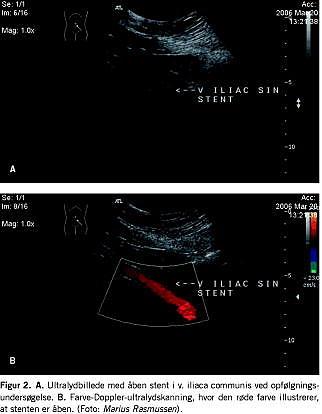

Postoperativ kontrol af patienterne skete efter seks uger, seks måneder, 12 måneder og efterfølgende hvert år. Ved hver kontrol blev patienterne vurderet klinisk, og der blev foretaget UL-undersøgelse af den behandlede ekstremitet (Figur 2 ). Her blev det vurderet, om venesegmentet med den anlagte stent var åbent, og patienternes veneklapfunktion blev undersøgt for at konstatere, om der var refluks i den pågældende ekstremitet.

Taksigelser: Tak til overlæge Marius Rasmussen, Sygehuset i Thorshavn, i forbindelse med efterundersøgelse af en patient på Færøerne samt levering af ultralydskanningsbilleder.